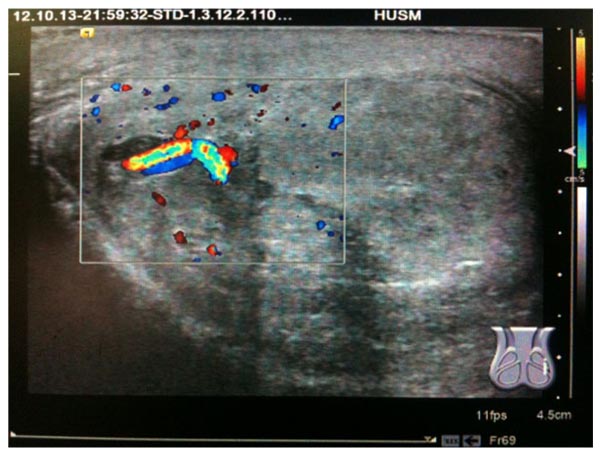

Ultrasound revealed the loss of normal configuration. The outline of the left testis was grossly enlarged, lobulated and heterogeneously hyperechoic with reduced vascularity at the affected area (Fig. 1). Furthermore, normal epididymis was not identified. The scrotal wall was grossly thickened and heterogeneous while spermatic cord showed normal vasculature (Fig. 2). However, the right testis retained normal configuration.

Exiting literature indicate the promising role of ultrasound along with physical examination as readily available noninvasive and highly accurate measures [1, 2]. However, there is a debate on the accuracy of ultrasound for testicular rupture due to its poor sensitivity [11] and misdiagnosis [12]. Nevertheless, more recent investigations reported acceptable sensitivity and specificity (95%) for diagnosing testicular rupture [1]. A great disparity in the management strategies of patients makes it difficult to evaluate the accuracy of ultrasound across published literature. In our institution all the patients with blunt scrotal trauma get benefits from the ultrasound. However, patients with abnormal clinical and ultrasound findings are managed surgically. In the current case, the results of scrotal ultrasound correspond to the intraoperative findings, reflecting the usefulness of ultrasound in the blunt scrotal trauma.